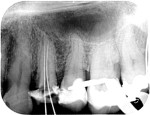

Re-treatments are more difficult than primary root canal work as the filling material has to be removed and any errors in the previous treatment corrected where possible.

Post removal cases